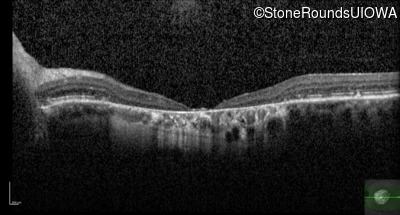

Optical Coherence Tomography - Left - 20/125

Exemplar / OCT Stack

OCT Stack